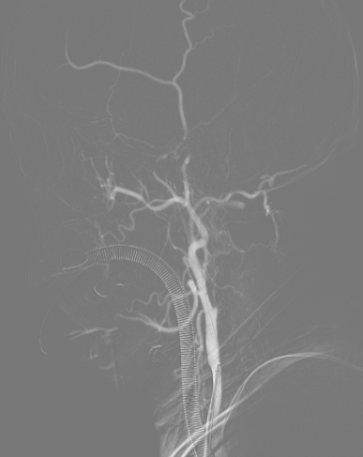

左侧颈总动脉造影可见颈内动脉闭塞,动脉末期可见颈外动脉经眼动脉向颈内动脉代偿,颈内动脉末端以远不显影。

在泥鳅导丝及5F MPA1造影管配合下将6F股动脉长鞘至于左侧颈总动脉行路图,在200cm Sur-reach®微导丝配合下将2.5*15mm颅内球囊扩张导管扩张后,将6F导管鞘通过颈内动脉起始部闭塞段,行路图可见颈内动脉颈段至海绵窦段后膝处血栓影,左侧大脑中动脉闭塞。

将6F Oneering®远端通路导管自颈段负压抽吸至左侧大脑中动脉M1段,抽吸出大量血栓。行路图提示颈内动脉及大脑中动脉通畅。

术后造影:可见左侧颈内动脉通畅,大脑前动脉不显影,因患者前交通动脉开放,未处理。